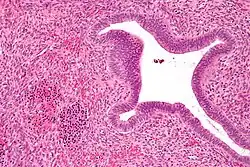

It is normal for infants have hepatic EMH as they are developing up until roughly 5 weeks of age.[13] On the other hand, hepatic EMH in adults can indicate a pathological state. This includes transplantation, hepatic tumors, hepatic disorders, or sepsis. Hepatoblastoma, adenomas and hepatocellular carcinomas can also lead to EMH in adults.[14][15] Additionally, EMH is often observed within the hepatic sinusoids.